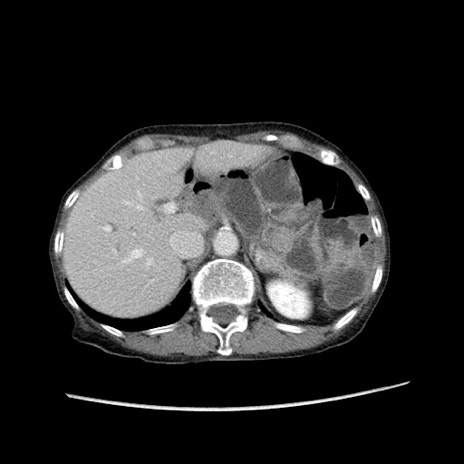

症例25(横断像)

【症例】80歳代女性

【主訴】胸のつかえ感

【現病歴】約9時間前に食後から胸のつかえた感じあり、嘔吐あり、来院。

【既往歴】胃癌(全摘)、胆摘、虫垂炎

【身体所見】心窩部に圧痛あり、反跳痛なし。

【データ】WBC 5700、CRP 0.05